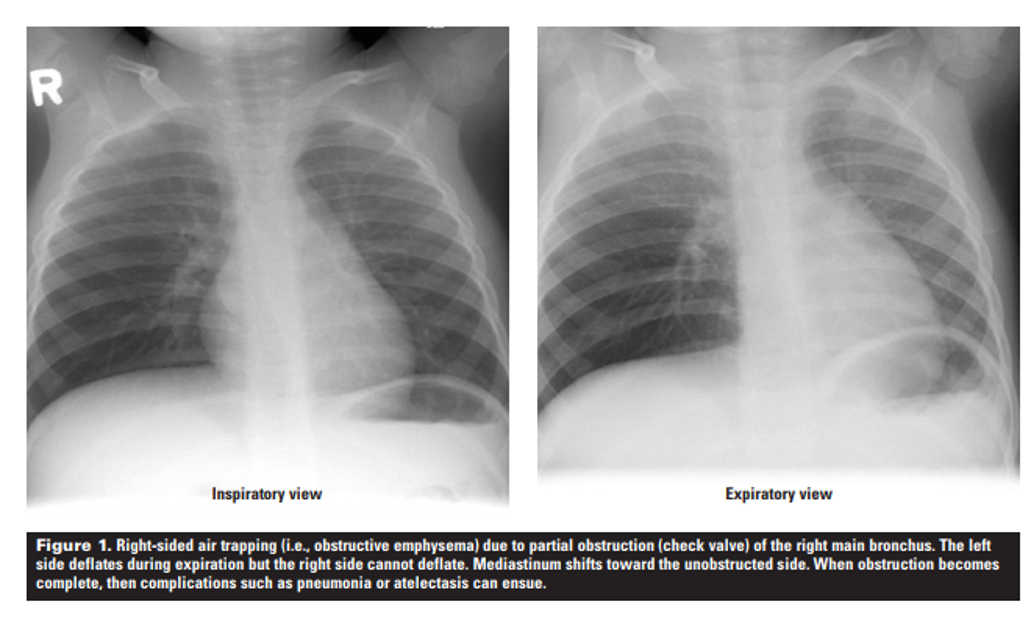

특수한 경우로, 숨을 내쉬고 찍는 경우도 있습니다. 주로 기흉(pneumothorax)이나 기도 내 이물질을 판단하기 위해 촬영 하는 경우가 있습니다(루틴하게 찍는 것은 아니고 긴가민가 할 때 추가 검사입니다). 기흉은 내쉬고 찍으면 폐가 더욱더 쪼그라들어 흉강내 공기 유무를 정확히 판단 가능합니다. 기도 내 이물질인 경우 정상적으로 쪼그라들어야 하는 폐가 기도내 이물이 공기 흐름을 막으면서 쪼그라들지 않아 진단 할 수 있습니다. 하지만 흔히 촬영하지는 않습니다.

왼쪽과 오른쪽 X-ray 비교시 좌폐는 호기시 용적이 감소하고 음영이 증가하지만,

우폐는 호기시에도 용적 변화가 없고 여전히 검다.

우폐 기관지에 이물이 있어 공기 흐름이 막힌다.

흉부 X-ray와 마찬가지로 어떤 경우는 내쉬고 촬영하기도 합니다. 주로 기도(airway) 병변이 있을 때 시행합니다. 정상적으로 내쉬고 찍으면 폐의 부피가 줄어들고, 공기 양이 줄면서 폐 실질이 들이쉴 때 보다 약간 하얗게 됩니다. 그런데 기도 병변이 있으면 폐의 부피가 줄어들지 않고, 공기가 빠져 나가지 않으면서 정상 부위에 비해 검게 보입니다. 이를 air trapping(공기걸림, 공기잡이)이라고 칭하고, 기도 병변을 나타내는 소견입니다. 주로 기관지확장증, 폐기종, 기도내 이물 등이 대표적입니다. 그 외에도 기관-기관지연화증(tracheobronchomalacia)에서 내쉬고 찍은 CT상 기도의 직경이 감소 하는 것을 확인 할 수 있습니다.

세기관지염 환자. 좌측 흡기 후 CT에서도 약간의 air trapping 이 보이긴 하나,

우측 호기 후 CT에서는 검게 보이는 air trapping이 명확히 보인다.